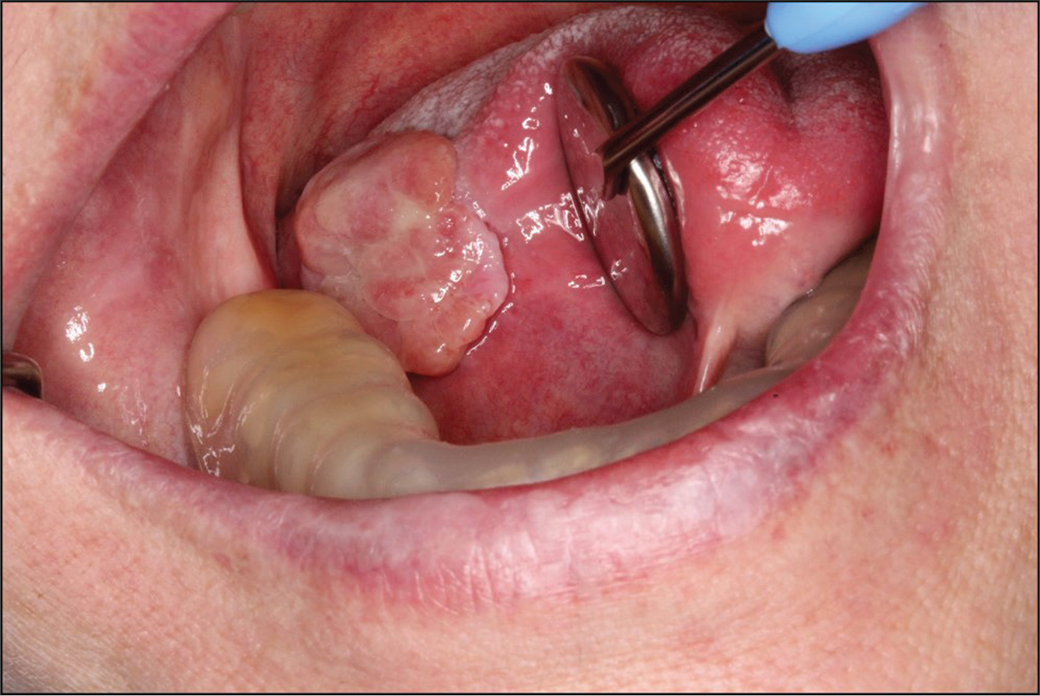

In June 2015, the patient reported increased pain from the enlarged ulcer without improvement of symptoms. A new excision was performed (Figure 2a), where HPE did not show any signs of dysplasia, but revealed an ulceration with fibrinous crusta, inflammation, and extensive infiltrates of neutrophil granulocytes (Figure 2b and c). At a revisit in September 2015, there was an ulcer with fungal infection. Fluconazole was administered, and the patient was called in for re-examination in December 2015. At that point, the lesion had developed an exophytic appearance on the lateral side of the tongue (Figure 3). In February 2016, treatment with radiofrequency ablation of the tongue was carried out (Figure 4). HPE displayed moderately to severely inflamed mucosa, with fibrosis and an ulcer consisting of eosinophil-rich infiltrates with candida infection. There were still no signs of malignancy or dysplasia. Antimycotics were administered.

Fig 3

Figure 3. In December 2015 the lesion had an exophytic appearance. A dental mouthguard can be seen covering the teeth of the lower jaw to protect the mucosa of the tongue.